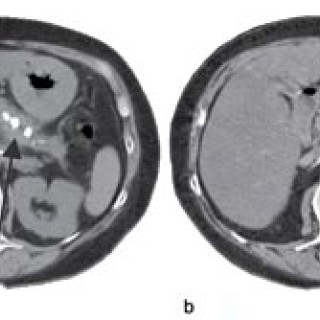

En 52 år gammel etnisk norsk mann ble innlagt i psykiatrisk akuttavdeling etter noen få uker med kraftig økende aktivitetsnivå. Han hadde vist markant endret atferd – blant annet hadde han satt seg fore å sykle åtte mil i kuldegrader og slaps. Ved innleggelsen var han irritabel og snakket fort og nærmest usammenhengende. Somatisk status presens ved innkomst samt orienterende nevrologisk status var normale. Vanlige blodprøver ved innleggelse, inklusive Hb, SR, hvite blodceller, kreatinin, natrium, kalium, ALAT, ASAT, ferritin, folat, kobalamin, FT4, TSH, var alle innenfor referanseområdet...